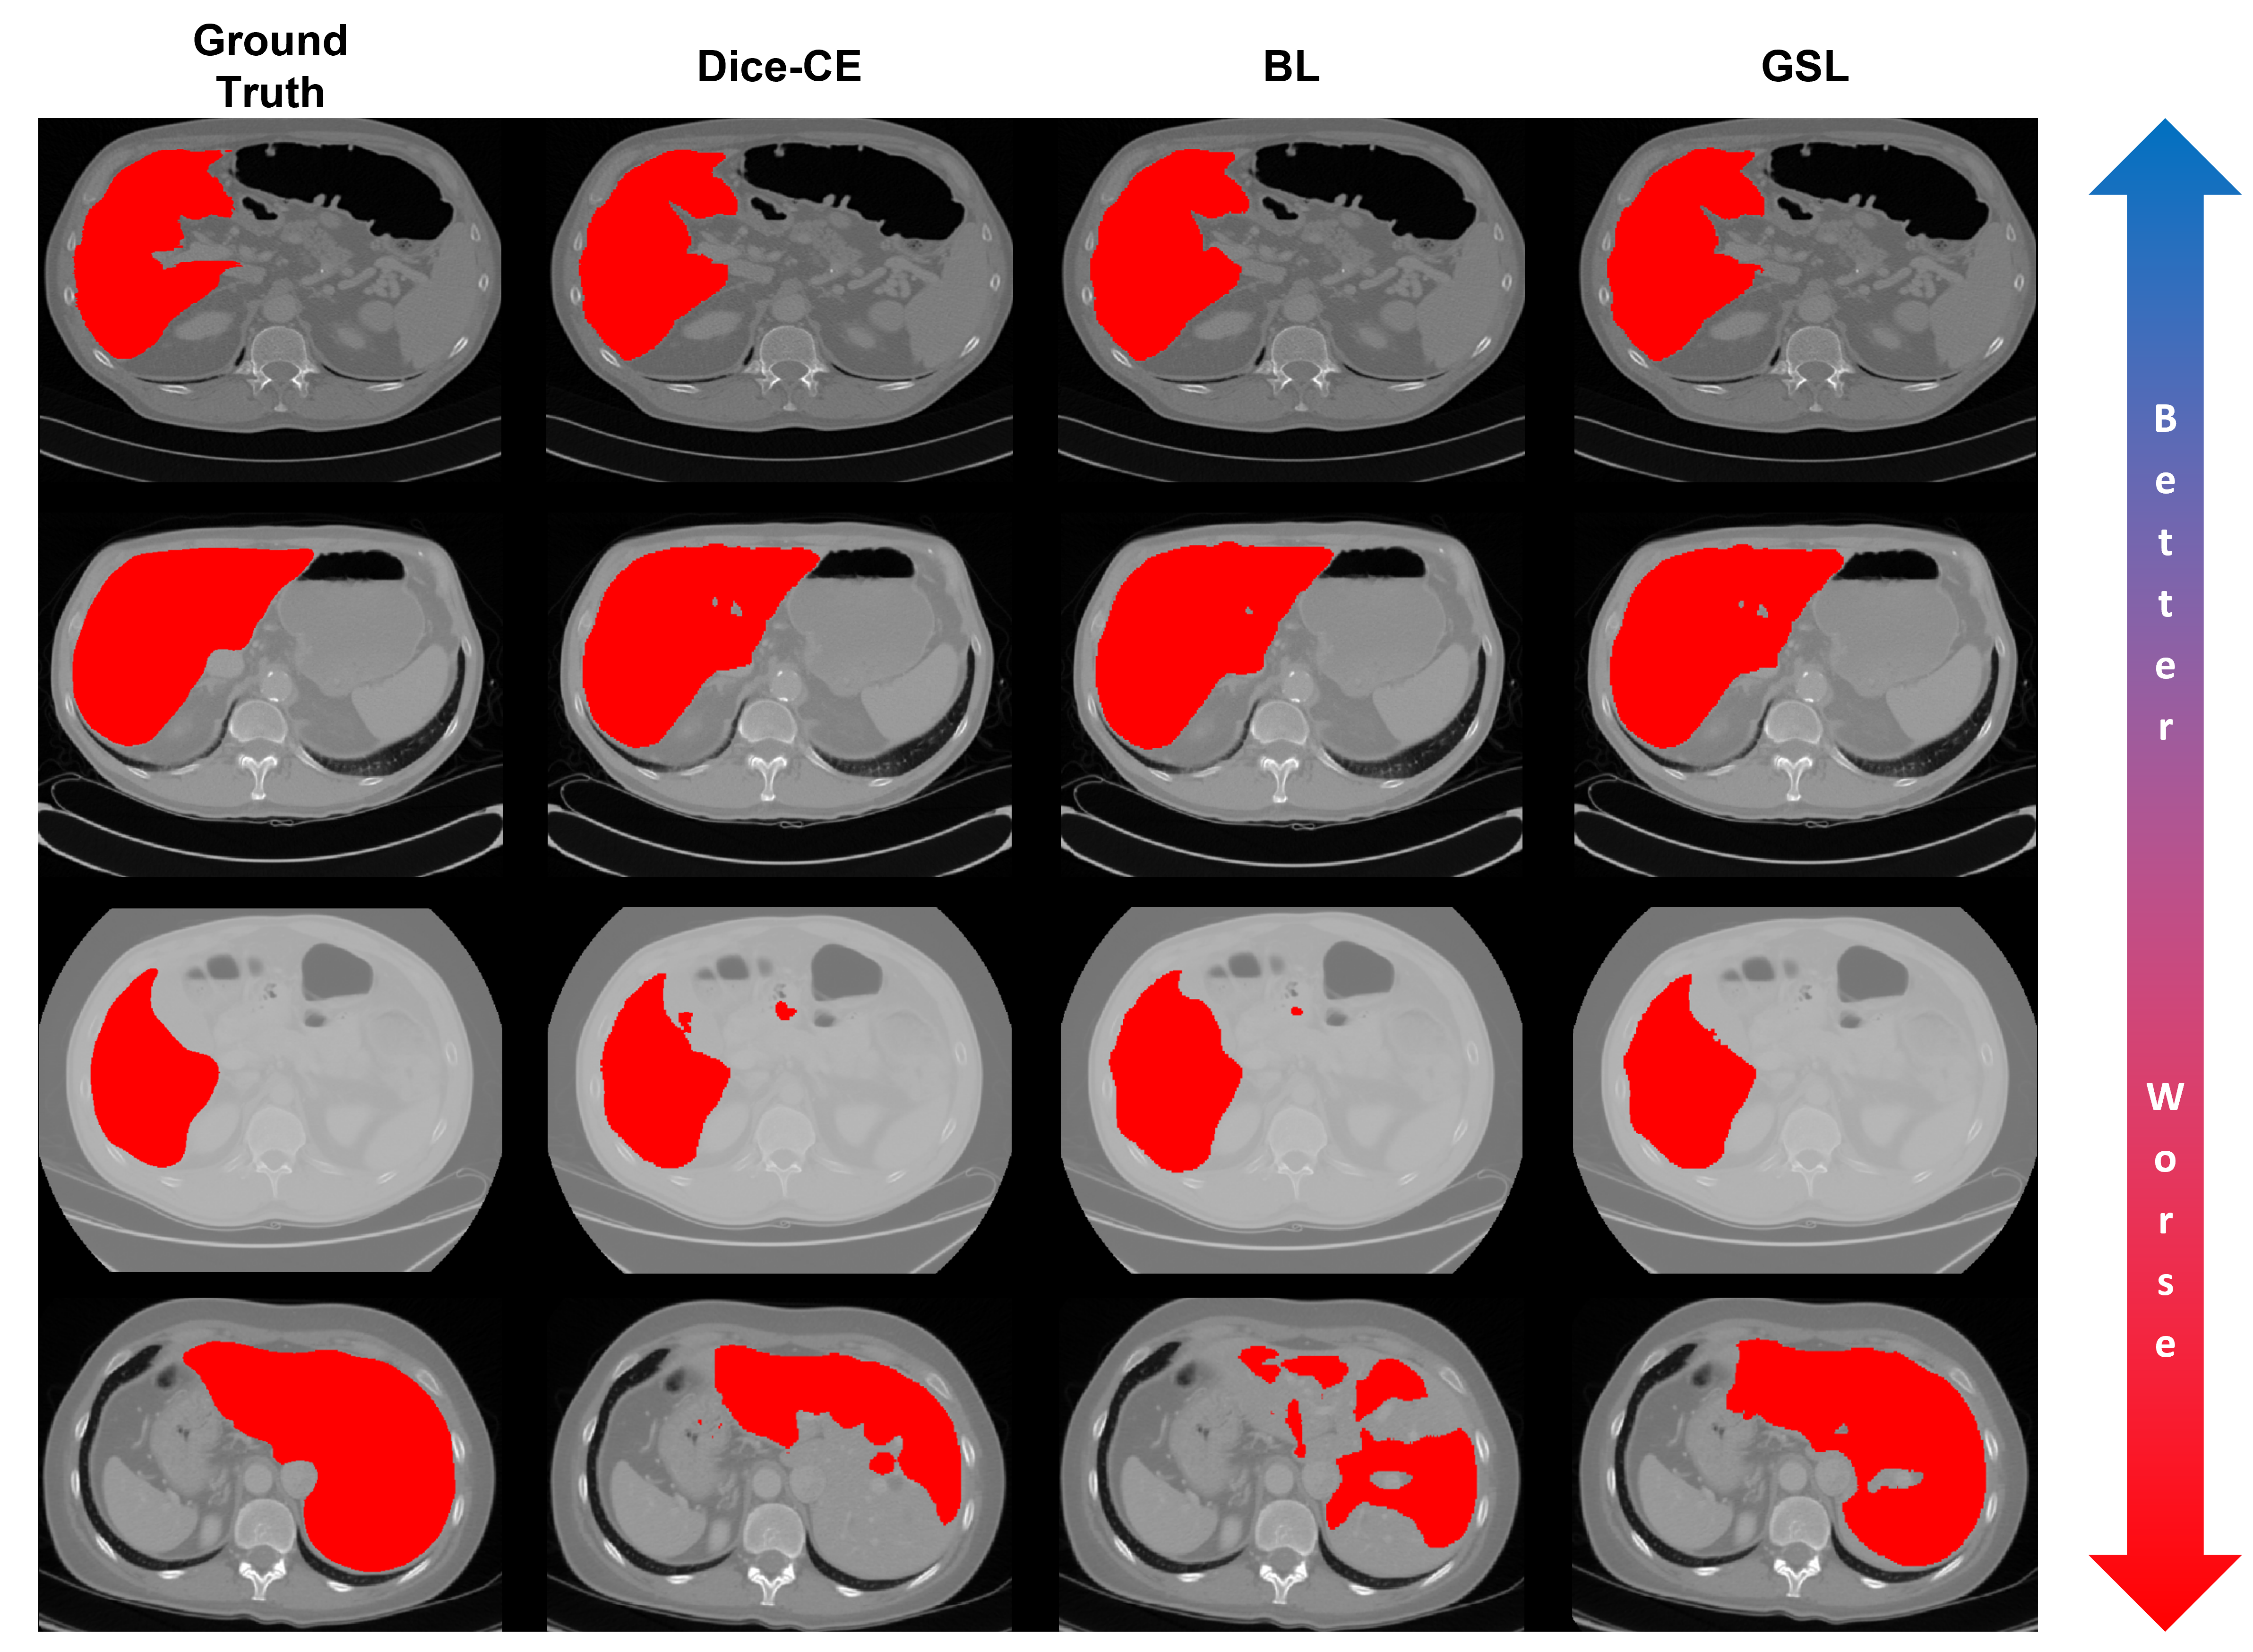

Using the methods described in Section 2, we train a nnUNet using each loss function described in Section 1.1 and compare their performance to our proposed GSL function. This experiment uses a linear schedule for the parameter α𝛼\alpha in the boundary-based losses (i.e., HL, BL, and GSL). Table 1 shows the results of this comparison. Here, our GSL achieves lower Hausdorff 95 and average surface distances for the LiTS and BraTS challenge datasets. Figures 3 and 4 show from left to right the ground truth and predictions from the nnUNet architecture trained on LiTS and BraTS data respectively, with the Dice-CE, BL, and GSL functions for a spectrum of easier to more difficult test cases. Even for more difficult cases, we see that the GSL produces visually superior predictions than the Dice-CE and BL functions.

Refer to caption

Figure 3: From left to right, ground truth and predictions from the nnUNet architecture trained on LiTS data with Dice-CE, BL, and GSL functions for a spectrum of easier to more difficult test cases. Here, we see that, even for more difficult cases, the GSL produces visually superior predictions than the Dice-CE and BL functions.